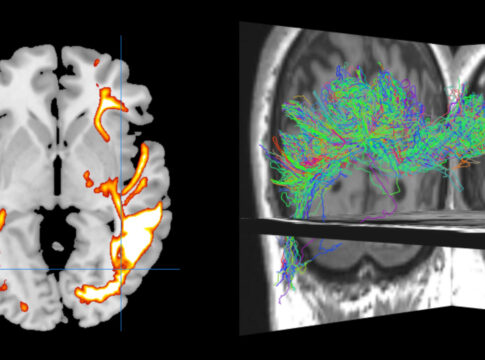

Imagerie du développement du système de défense du cerveau